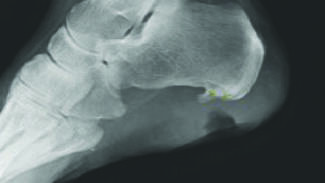

Even when biopsies are initially negative, it is important to maintain an index of suspicion for alternative diagnoses. In this article, the authors share a relevant case that highlights this process, and the multidisciplinary approach that...